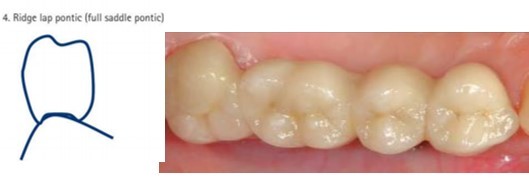

ridge lap/saddle pontic design

greatest contact with soft tissue

if designed carefully: can be cleansed

less food packing than ridge-lap

care taken not to displace soft tissue or cause blanching of tissue